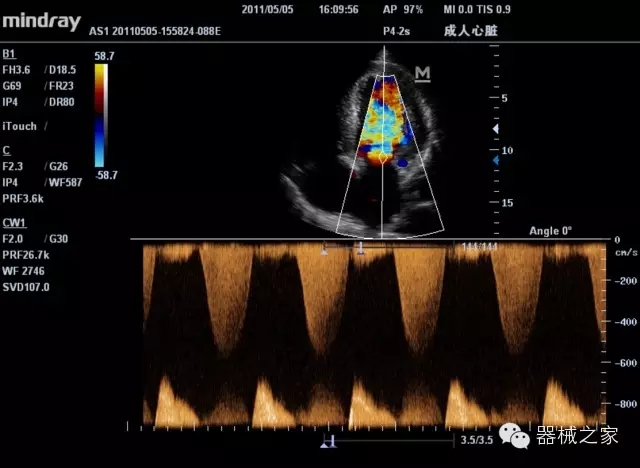

臨床圖片賞析

產(chǎn)品特點

·裝載有采用Multi-Core多核處理的非嵌入式平臺,成像效率大大提高,并且能夠給用戶帶來高速、多任務(wù)并行信號處理體驗;

·優(yōu)秀的圖像效果、強大的功能體驗、豐富的探頭選擇、合理的便攜式設(shè)計,全中文顯示及病人管理界面,使得M7在任何場合、任何時候都能快速響應(yīng)更好的心血管、腹部、婦產(chǎn)、小器官等常規(guī)超聲檢查以及肌骨、神經(jīng)、顱腦、術(shù)中等新興領(lǐng)域的使用需求;

8倍波束并行處理系統(tǒng)

·在便攜式緊湊平臺上采用更多倍波束并行接收信號處理模式,無論二維還是彩色血流圖像狀態(tài)下,擁有更靈敏的回波頻移捕獲能力,大大提高時間分辨率,尤其使得心血管表現(xiàn)更為突出;

PSHI?寬帶頻移諧波技術(shù)

·在普通組織諧波的基礎(chǔ)上,通過精確控制的波束形成器,發(fā)射兩組具有相位偏差反向的信號,并采用并行信號處理,數(shù)字化合成并采樣回波信號,在高靈敏度的濾波器的處理過程中獲取更純凈的諧波信號,使圖像具有更加出眾的細節(jié)分辨率;

iClear®+iBeam?

·智能化按線復(fù)合多角度獲取聲束的原始信號,配合智能化的斑點噪聲識別及控制處理技術(shù),整體提高組織結(jié)構(gòu)細節(jié)分辨率,任何時候都能快速響應(yīng),更好的滿足心血管的使用需求;

支持全新3T工藝探頭群

·包括探頭材料、結(jié)構(gòu)設(shè)計、加工工藝三方面的革新技術(shù)給圖像帶來品質(zhì)的飛躍;